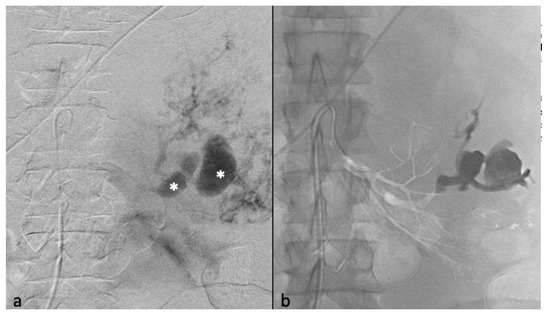

Figure 3.

Transarterial embolization (TAE) of an AML with massive aneurysms. (a) Angiography shows one AML on the upper pole of the left kidney with massive aneurysms (*) (b) Final control after TAE of the main arterial branch with ONYX 18 (6% EVOH) and technical success (lack of opacification of the AML).

Postembolization angiography performed through the 6-F catheter confirmed successful occlusion of the artery and the patency of other renal arteries branches. Technical success was defined as no opacification of the main feeding arteries and lack of AML staining on the post-TAE angiography after one embolization (primary technical success) or two (secondary technical success) (Figure 3).